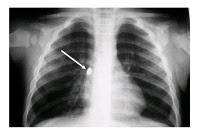

Caso 1

Como veo que les gusta, de vez en cuando, hacer de médicos de guardia aquí les pongo dos radiografías. Ustedes están de guardia un sábado de madrugada y se en cuentran frente a estas dos situaciones. En cada una de ellas me han de decir lo que ven, qué puede haber ocurrido y cómo "arreglamos" a estos angelitos. Ninguno de estos dos niños estaba en fermo pero uno de ellos tuvo que pasar por el quirófano. ¿Cuál y porqué?Suele ocurrir por descuido de los padres o de forma accidental pero el "trasiego" que pueden povocar es de órdago. Vigilen y estén atentos con sus vástagos; todo lo que entra por la boca...